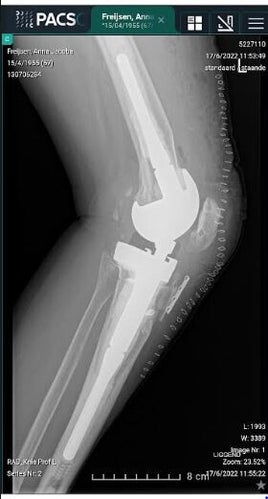

Op 16 juni kreeg ik mijn 5de en laatste knieprothese ingeplant. Het zou de zwaarste hynchprothese zijn. Als deze mislukt gaat de amputatie door.

Na elke knieprothese begint mijn knie na 2 à 3 maanden tekenen van loosening te vertonen. Wat blijkt nu... mijn knie zit al lichtjes los en blijkbaar slingert mijn been een beetje bij het stappen. Dat begint al héél vroeg nu, precies 14 dagen na mijn operatie. Nochtans doe ik braaf mijn oefeningen.

Even terug naar het doorzakken van mijn knie. Direct ijs gelegd na de therapie maar tegen de avond begon de pijn heviger te worden en m'n knie dikker. Daags nadien platen laten nemen en moet vandaag geduldig wachten op de uitslag.